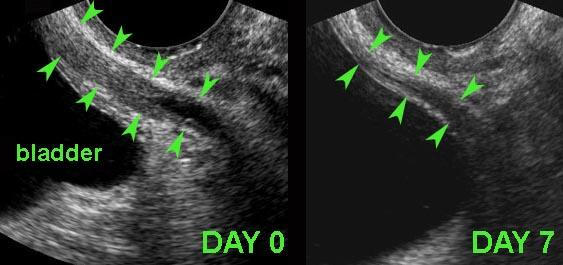

Các ổ lạc nội mạc tử cung trên bề mặt ngoài của đại tràng ở bốn bệnh nhân khác nhau.

Các ổ lạc nội mạc tử cung (*) trong túi cùng Douglas là các khối đặc, giảm âm, kém mạch máu, khu trú không đối xứng, liên tục với lớp cơ giảm âm phía ngoài của đại tràng.

Lớp dưới niêm mạc tăng âm phía trên và niêm mạc đại tràng thường còn nguyên vẹn. Điều này cũng giải thích tại sao máu trong phân khá hiếm gặp trong DIE.

Bờ ngoài của các khối giảm âm này thường dính chặt vào tử cung và/hoặc cổ tử cung. Thường có thể thấy hình ảnh tua gai hoặc “kéo căng” ở các bờ ngoài.